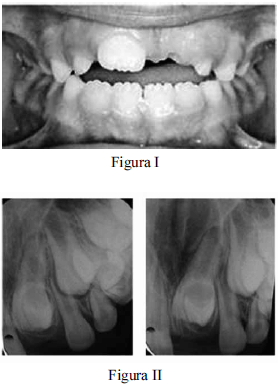

Uma paciente de seis anos de idade foi levada a um consultório odontológico para a realização de uma consulta de rotina. Ao examinar a arcada dentária da criança, o cirurgião-dentista observou que, apesar de ter havido a erupção do dente 11, ainda não havia ocorrido a erupção do elemento 21, conforme mostrado na figura I. Após a realização de radiografia da região periapical, constatou-se a presença de dente supranumerário impedindo a erupção do elemento 21, conforme apresentado na figura II, motivo pelo qual o cirurgião-dentista recomendou a remoção cirúrgica do dente supranumerário.

Tendo como referência as imagens apresentadas, julgue o item subsecutivo, relativo ao caso clínico descrito.

Se a exodontia não for realizada na paciente desse caso clínico, haverá possibilidade de os mesiodentes inclusos retardarem ou impedirem a erupção dos dentes permanentes sucessores, bem como de causarem desvios de erupção, giroversões, reabsorção radicular de dentes adjacentes e formação de cistos com destruição óssea.